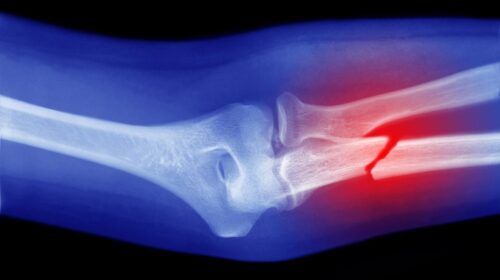

వైద్యరంగంలో చైనా శాస్త్రవేత్తలు మరో గొప్ప ఆవిష్కరణను వెలుగులోకి తెచ్చారు. విరిగిన ఎముకలను అతికించడానికి గంటల తరబడి శస్త్రచికిత్సలు, స్టీల్ ప్లేట్లు, స్క్రూలు అవసరం లేకుండా, కేవలం మూడు నిమిషాల్లోనే ఆ పనిని పూర్తి చేసే ఒక ప్రత్యేకమైన ‘బోన్ గ్లూ’ను అభివృద్ధి చేశారు. ఇది ఆర్థోపెడిక్స్లో ఒక విప్లవాత్మకమైన మార్పు అని నిపుణులు భావిస్తున్నారు.

తూర్పు చైనాలోని షెజాంగ్ ప్రావిన్స్కు చెందిన పరిశోధకులు దీనికి ‘బోన్ 02’ అని పేరు పెట్టారు. సముద్రంలోని ఆల్చిప్పలు నీటిలో కూడా గట్టిగా అతుక్కునే లక్షణం నుంచి ప్రేరణ పొంది ఈ జిగురును రూపొందించారు. దీనిపై పరిశోధనకు నాయకత్వం వహించిన సర్ రన్ రన్ షా ఆసుపత్రి అసోసియేట్ చీఫ్ ఆర్థోపెడిక్ సర్జన్ లిన్ షాన్ఫింగ్ ఈ ఆవిష్కరణ వివరాలను పంచుకున్నారు.

ఈ జిగురును విరిగిన ఎముకల ప్రదేశంలోకి ఒక సూది ద్వారా సులభంగా ఇంజెక్ట్ చేయవచ్చని, ఇది కేవలం రెండు, మూడు నిమిషాల్లోనే ఎముకలను అతికించగలదని ఆయన వివరించారు. తీవ్ర రక్తస్రావం జరుగుతున్న ప్రదేశంలో కూడా ఇది సమర్థవంతంగా పనిచేస్తుందని ఆయన తెలిపారు.